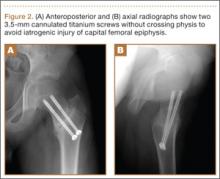

A 10-year-old boy was brought to our emergency department with the chief complaint of left hip pain after a car accident. Anteroposterior and axial lateral radiographs showed a displaced cervicotrochanteric femoral neck fracture (Figures 1A, 1B). The patient was admitted to the hospital and underwent closed reduction and internal fixation with two 3.5-mm cannulated titanium screws within 12 hours of arrival. The screws did not cross the physis to avoid iatrogenic injury of the capital femoral epiphysis (Figures 2A, 2B). The entry point was located at the lower level of the lesser trochanter. The lateral cortex was penetrated only once by the guide wire for the placement of each screw.